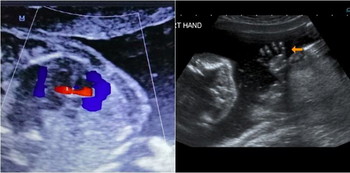

- Jantung – kedudukan jantung, saiz, “bilik-bilik” jantung, “dinding” jantung, injap, beberapa salur darah utama.

Major congenital heart defect | Masalah jantung serius | 25% |